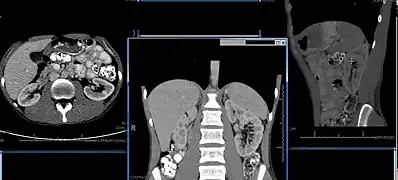

Normal adult right kidney as seen on abdominal ultrasound with a pole to pole measurement of 9.34 cm

Imaging

Renal ultrasonography is essential in the diagnosis and management of kidney-related diseases.[46] Other modalities, such as CT and MRI, should always be considered as supplementary imaging modalities in the assessment of renal disease.[46]